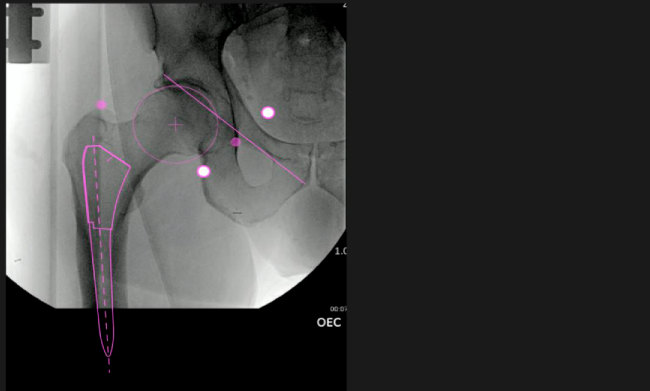

Nuestro navegador de cadera VELYS HIP NAVIGATION ™ es una solución digital que te acompañará a mejorar cada paso de las fases operatorias.

El sistema de navegación digital VELYS HIP NAVIGATION ™ para cirugía de cadera, es una tecnología innovadora y no invasiva diseñada para potencializar la toma de decisiones en tiempo real y basada en datos; aumentando la precisión y mejorando los resultados a corto, mediano y largo plazo para los pacientes.

Aumenta la precisión y reproducibilidad quirúrgica generando resultados predecibles.

Datos procesables en tiempo real para la toma de decisiones.